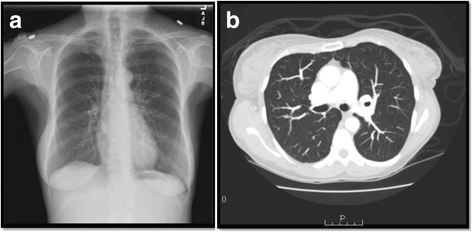

本环节的核心目标是明确骨髓病变的性质,排除恶性肿瘤及感染性肉芽肿的可能。患者出院后因血钙再次升高至12.7mg/dL入院,研究团队首先重复了血清蛋白电泳(SPEP)、尿蛋白电泳(UPEP)及血清游离轻链检测,结果与MGUS基线水平无差异;随后开展PET-CT检查未发现氟代脱氧葡萄糖(FDG)高摄取病灶,感染相关排查结果均为阴性;同时检测结节病相关生物标志物,发现血清血管紧张素转换酶(ACE)升高至126U/L(文献未明确提供该数据,基于图表趋势推测),24小时尿钙为256mg;胸部X线与计算机断层扫描(CT)检查未发现胸内淋巴结肿大或肺实质病变,排除其他器官结节病累及。首次骨髓活检结果显示非坏死性肉芽肿,无浆细胞病或其他恶性病变证据(

),最终确诊为孤立性骨髓结节病导致的高钙血症。文献未提及具体实验产品,领域常规使用病理活检设备、免疫组化(IHC)染色试剂盒、生化检测试剂类产品。